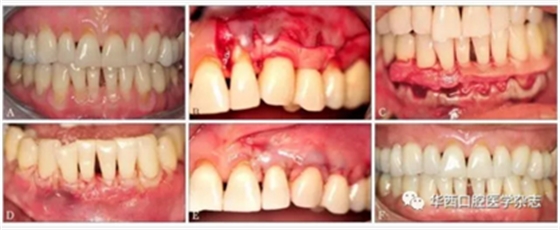

尽管使用ADM进行膜龈手术的长期疗效一直存在争议,但目前该技术仍是除游离结缔组织外的另一个疗效较为可靠的根面覆盖手术(图1)。

A:患者有广泛性牙龈进行性退缩,牙根暴露、敏感,临床附着水平丧失,附着龈丧失;B、C:手术采用半厚瓣,翻过膜龈联合线,常规根面处理,采用5-0可吸收线用连续褥式缝合方式将ADM缝合在唇颊侧;D、E:无张力情况下,采用5-0可吸收线行连续褥式缝合,半厚瓣冠向复位将ADM完全覆盖;F:术后20个月,由于大量牙槽骨吸收,牙根表面没有达到完全覆盖,但是角化组织(附着龈)增加了3~4 mm。

图 1 ADM结合冠向复位瓣手术